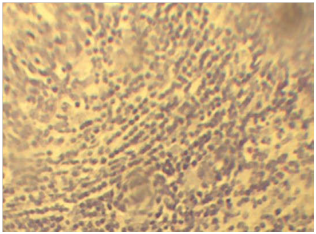

The most characteristic microscopic lesion was tubercle granuloma with central necrosis and calcification. The central area is made of necrotic cellular debris, calcium deposits, and connective tissue capsule walled off the granuloma from the surrounding tissue. The next layers from center to outer were made up of lymphycytes, macrophages, epitheloid macrophages distributed under connective tissue layers (Figure 4A). The frequency of characteristic tubercle granuloma was 4.7% (26/556) (Figure 4B). The presence of concomitant pyogranulomatous and granulomatous lesions in different organs was observed in 7.1% (40/556). Some granulomas were characterized by necrotic foci and intense calcification and fibrosis with absence of epithelioid cells. Multiple small granulomas in the lymph node (Figure 5) with less dense lymphocyte at periphery and epitheloid cells surrounding the deep outer lymphatic layer of the granuloma.

Figure 4 A) Characteristic epitheloid macrophages in the lymph nodes. Note; The epitheloid macrophages shown as elongated (Blue arrow) and the lymphocytes in the next layers (black arrows). H & E stains (10x). B) The characteristic granulomas in the lymph node with calcium deposits (red arrow) at the center, followed by sever necrosis and cellular debris (black arrow) immediate to calcium deposits. H & E stain (10x).